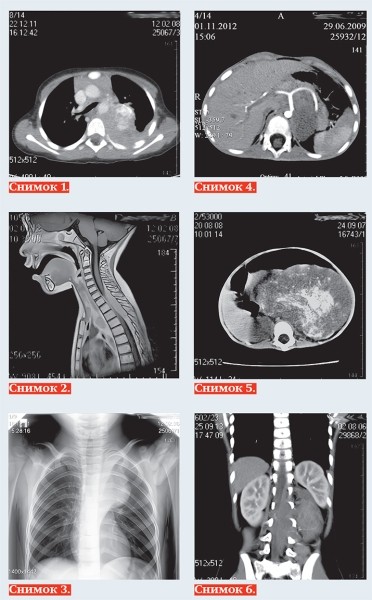

Тканевыми характеристиками нейробластомы являются: мягкотканная масса +25+35 HU на КТ (снимок 1), с гипоинтенсивным МР-сигналом на Т1-ВИ, изо/слабогиперинтенсивным сигналом на Т2, Т2 dark fluid — ВИ (снимок 2), негомогенная за счет кровоизлияний, очаговой кальцинации и некротических изменений, с умеренным контрастированием в паренхиматозную фазу, умеренной рестрикцией диффузии на МРТ.

Современная методика МРТ-диффузионного исследования всего тела нацелена на поиск метастазов опухоли. Радионуклидное исследование с I123-метайодбензилгуанидином (MIBG) выявляет и уточняет жизнеспособность опухоли с наибольшей чувствительностью (90 %) и специфичностью (до 100 %). Позитронно-эмиссионная томография с фтордезоксиглюкозой (ПЭТ-ФДГ) используется для дифференциальной диагностики нейроэндокринных опухолей.

В руководстве Международной группы по изучению нейробластомы (Guidelines International Neuroblastoma Risk Group INRG-2009) предложена новая система стадирования опухоли, основанная исключительно на визуально определяемых признаках риска (Image Defined Risk Factors IDRF Staging System), а не на постоперационных данных, которые использовались в классификациях до недавнего времени.

Чаще всего нейробластома локализуется паравертебрально в реберно-позвоночной борозде по ходу симпатических ганглиев: в забрюшинном пространстве, надпочечниках, заднем средостении (снимок 3), полости таза, в области шеи. Генерализация опухоли с метастазированием в кости выявляется в 20 % случаев, в печень — 10 %, реже в легкие, головной мозг, подкожную клетчатку, при этом характерно поражение периорбитальных мягких тканей (1–5 %).

К наиболее важным визуально определяемым признакам опухоли (IDRF) относятся: поражение двух и более частей тела, вовлечение в опухоль более 50 % периметра артериального сосуда

(снимок 4), сдавление вены без визуализации ее просвета, инфильтрация прилежащего органа (снимок 5), компрессия трахеи и главных бронхов, инвазия сосудистых ножек почек, распространение в спинно-мозговой канал более трети просвета (снимок 6).